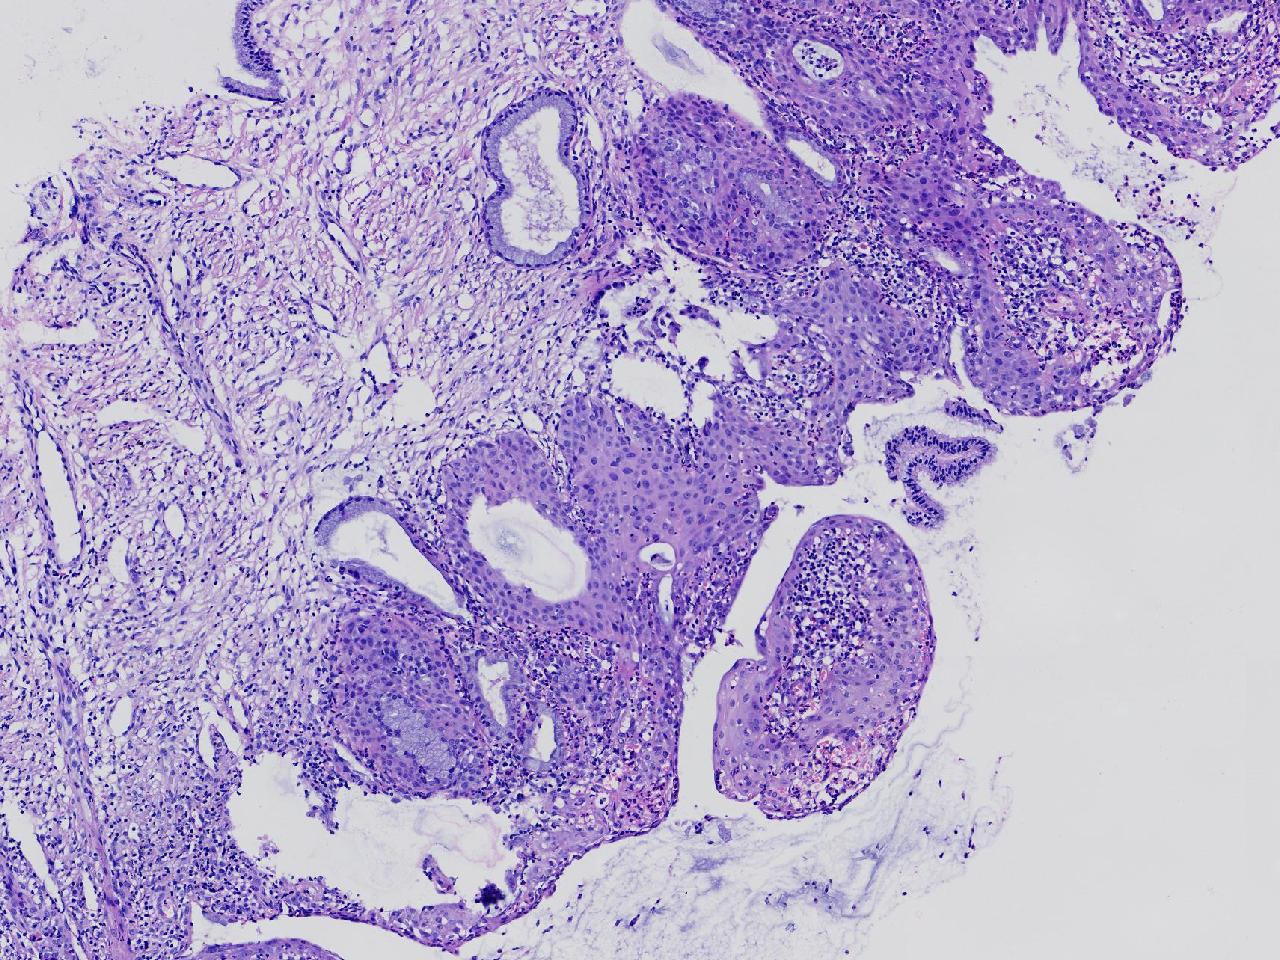

宫颈活检,有没有CIN?

女

36岁

宫颈病变

TCT示:ASC-US,HPV不详。

宫颈活检

慢性宫颈炎伴腺上皮鳞化。

(宫颈活检组织) 慢性炎,储备细胞增生伴鳞化。